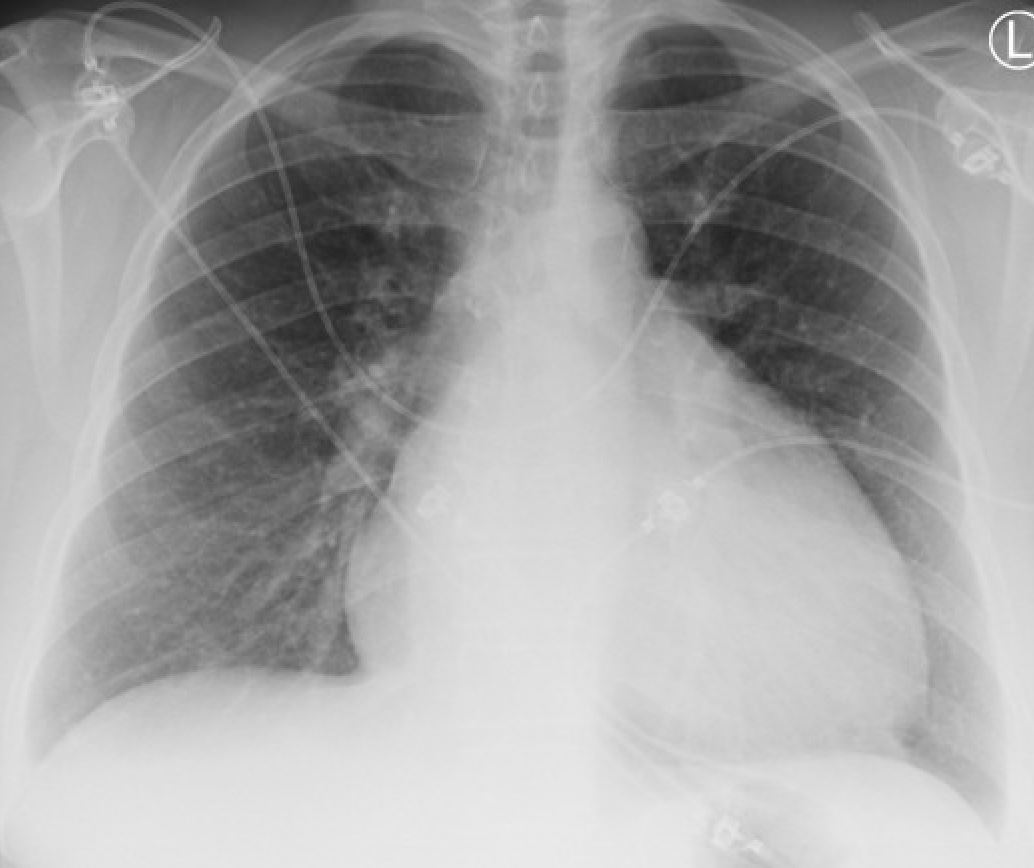

CXR:

…Formally reported as normal.

Mild ascites (splenorenal space shown) and mild bilateral pleural effusions are seen. POCUS is much more sensitive for effusions than CXRs.